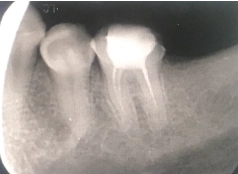

• Tình trạng răng trước đây:Mất răng số R37

• Bác sĩ chỉ định:Cấy ghép 1 trụ Implant

• Implant sử dụng:Implant Mis C1 Đức

• Răng sứ sử dụng:Răng sứ Zirconia Đức

Anh Tiến chia sẻ về tình trạng răng trước đây của mình: “Anh bị mất răng dưới cùng, lúc đầu cũng chủ quan, không làm gì hết. Sau một thời gian thì mới thấy răng đối diện trồi xuống. Anh mới ý thức được nếu để lâu nó sẽ không tốt, ảnh hưởng tới những răng khác”.

Cảm nhận được sự gần gũi và trình độ chuyên môn tốt của bác sĩ Thanh Phong, nên anh Tiến đã tự tin, sẵn sàng tiến hành trồng răng Implant, khôi phục lại hàm răng chắc khỏe. Kết quả nhận được cũng đúng như mong muốn của anh. Trụ Implant tích hợp thành công vào xương hàm, thay thế cho chân răng thật một cách vững chắc và giúp anh ăn uống thoải mái hơn rất nhiều.